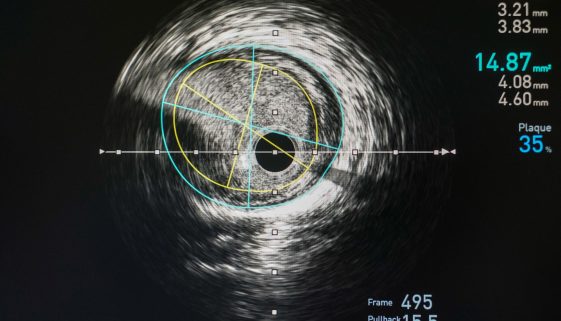

تُعد القسطرة العلاجية للشرايين الطرفية من الإجراءات الطبية المهمة التي تُستخدم لعلاج انسداد أو ضيق الشرايين في الأطراف، مثل الساقين والذراعين. يمكن أن تؤدي هذه الحالات إلى مشاكل صحية متعددة، بما في ذلك الألم والتعب والإصابة بالقرح. في هذه المقالة، سنقدم لك نصائح وتعليمات تثقيفية مهمة لتوضيح هذا الإجراء للمرضى […]